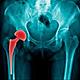

ARTROPLASTIA ACTUAL

Se continua investigando en la actualidad la mejora de los reemplazos, así mismo en la ultima actualización de las protesis, se implementan nuevos elementos como cromo, cobalto,ceramicos y el anteriormente mencionado cemento oseo para la fijacion, asi mismo un vastago mas largo y mejor adaptable